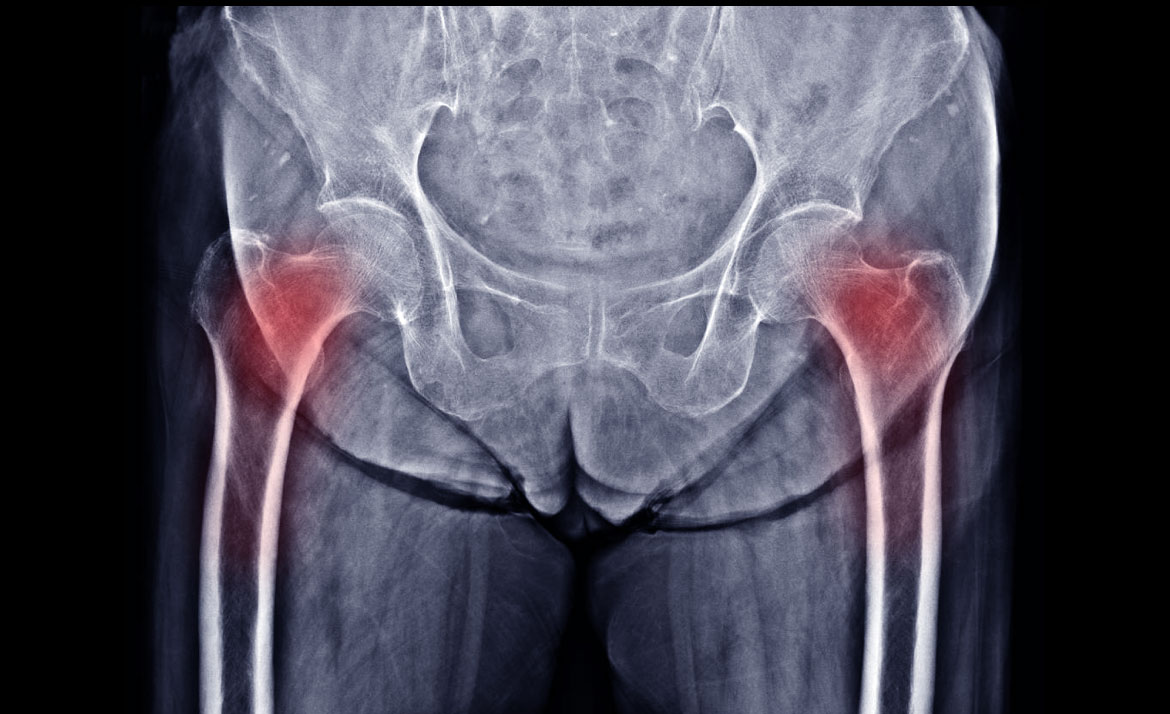

Osteoporosis is a condition that results from low levels of calcium in the bones (low bone density). The bones are consequently more fragile and fracture more easily and frequently than normal bones. Typically, the spine and hips are evaluated but, on occasion the forearms might be as well.